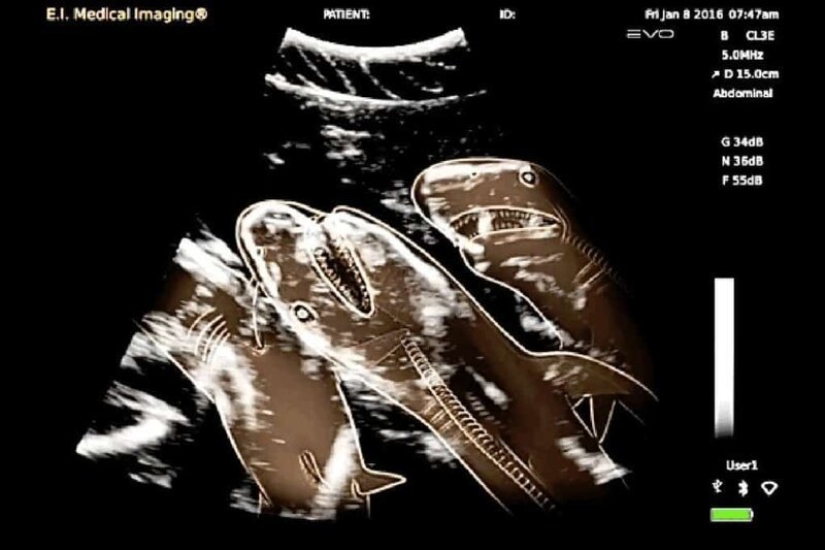

Ultrasonido de una tiburón preñada